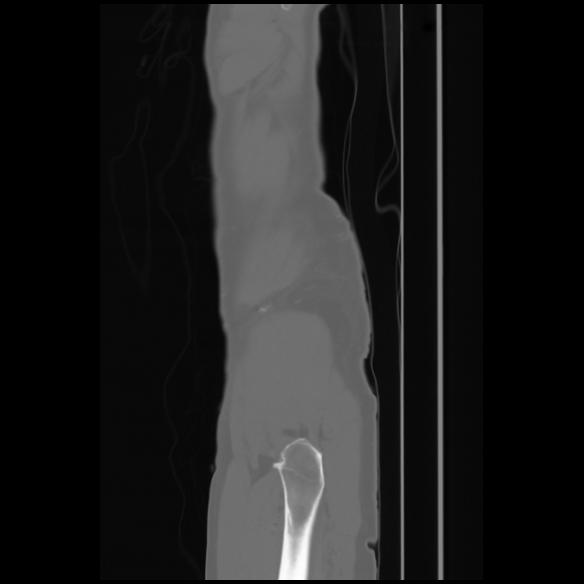

7 CUERPO,CE,Sagittal,3.000,CUERPO,Sagittal,